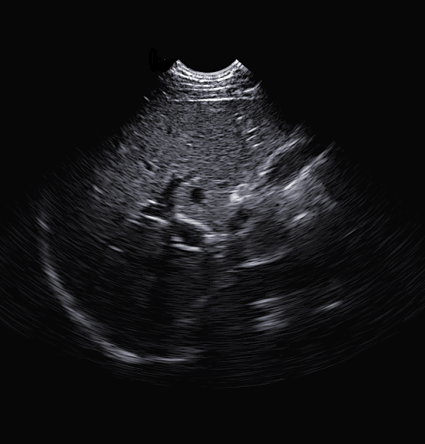

Scan Result

Liver Imaging